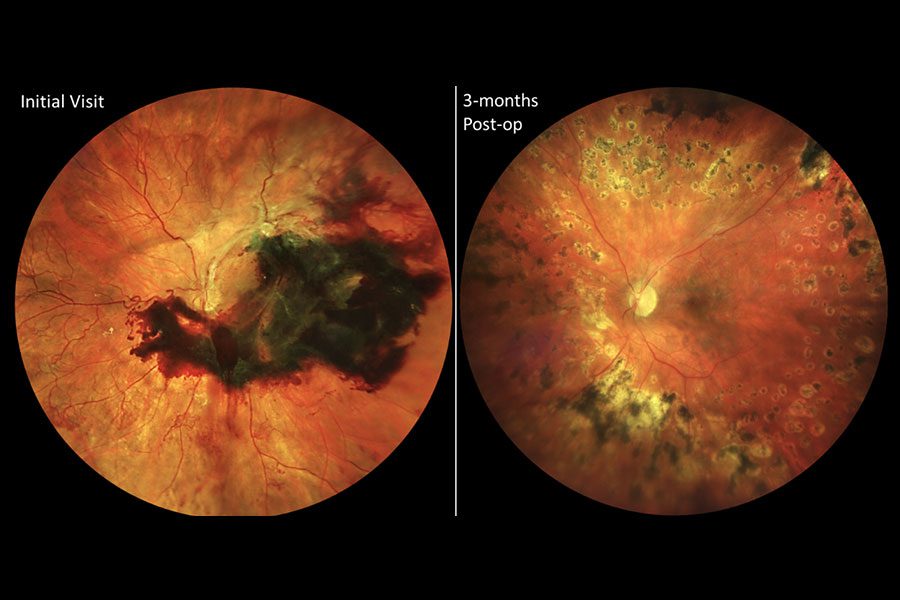

| Figura 2. Este paciente presentó PDR en ambos ojos, lo que se muestra en las imágenes del fondo de ojo preoperatoria tomadas en abril de 2017 (columna de la izquierda). Después del tratamiento con anti-VEGF, la PDR ya no aparece en las imágenes del fondo de ojo un mes después (columna de la derecha). Foto: Jennifer I. Lim, MD. |